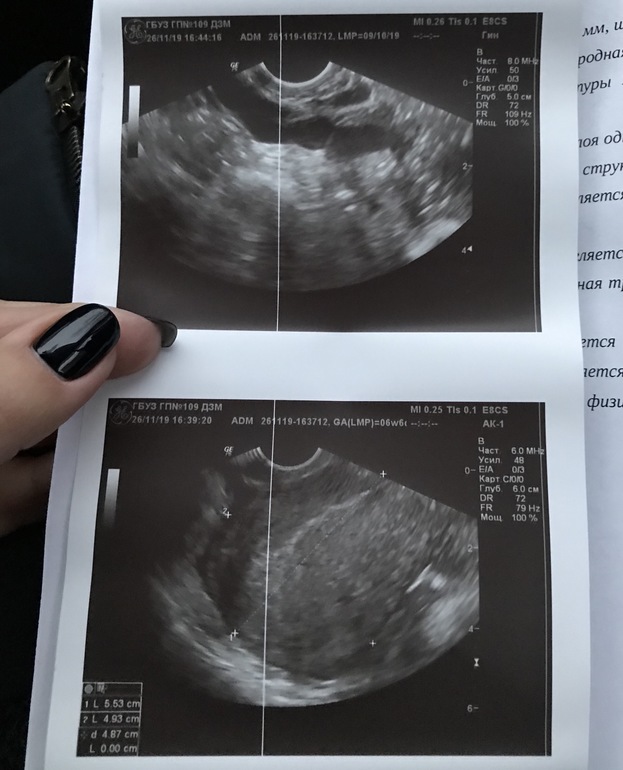

Писала про ХГЧ ранее, НОВОСТИ ПО УЗИ , кто силён или понимает в узи?!

Очень очень переживаю за вас. Хорошо, что в больнице вы. По узи смущает, что видно трубу на узи, обычно они не видны, а тут с анэхогенным содержимым, как будто в ней что-то есть и расширена на всем протяжении, как бывает при воспалении(( ПЯ тоже анэхогенно, но обычно его называют анэхогенным образованием с гиперэхогенным ободком. Может, еще не видно его на таком сроке в матке... Узисты тоже ошибаются. Хоть бы все хорошо было

посл.менстр.скорее всего 10.10.,а не 10.09. перепутали просто. Но эндик 6 мм,может ли быть Б с таким тонким((

Меня смущает только что труба увеличена. А ПЯ можно и позже увидеть, срок ещё маленький.